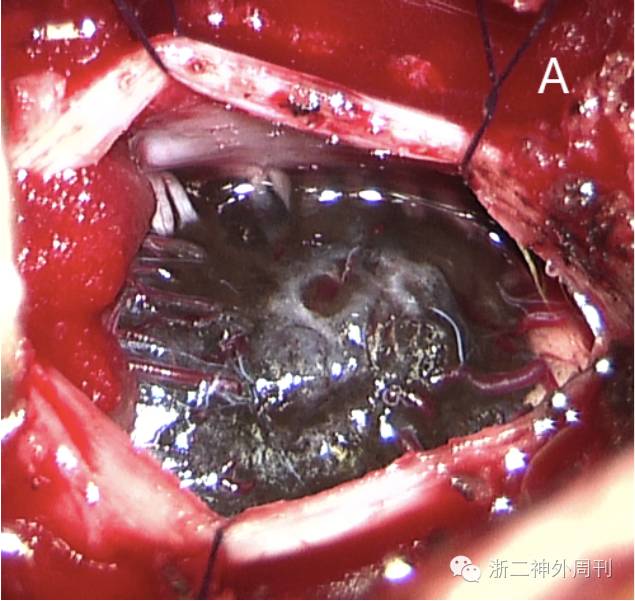

患者于4月前无明显诱因下出现左上肢麻木,间歇发生,无四肢乏力及大小便障碍等,未予重视。近来症状缓慢加重,来我院检查,颈椎增强MRI提示:C1-2髓内占位,性质待查(图1)。发病来除左上肢麻木以外,无其他不适。

1.颈椎增强MRI,见C1-2偏左侧髓内占位,呈嵌入式生长,向后凸出髓外。AB:平扫,病灶T1呈不均质高信号,T2呈低信号;CD:增强后强化明显。